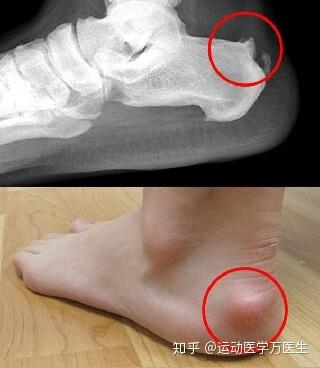

跟腱后滑囊炎痛点图

跟腱后滑囊炎痛点图,跟骨滑囊炎的症状图片

跟后痛和跟骨病,跟后痛可以有跟后滑囊炎,有跟后滑囊炎,跟腱止点撕裂

止点性跟腱炎haglund畸形与跟腱滑囊炎

2,跟腱附着在脚后跟部位的疼痛 3,脚后跟肿胀 4,脚后跟皮肤发炎,肿胀

疼痛解剖学|跟腱炎